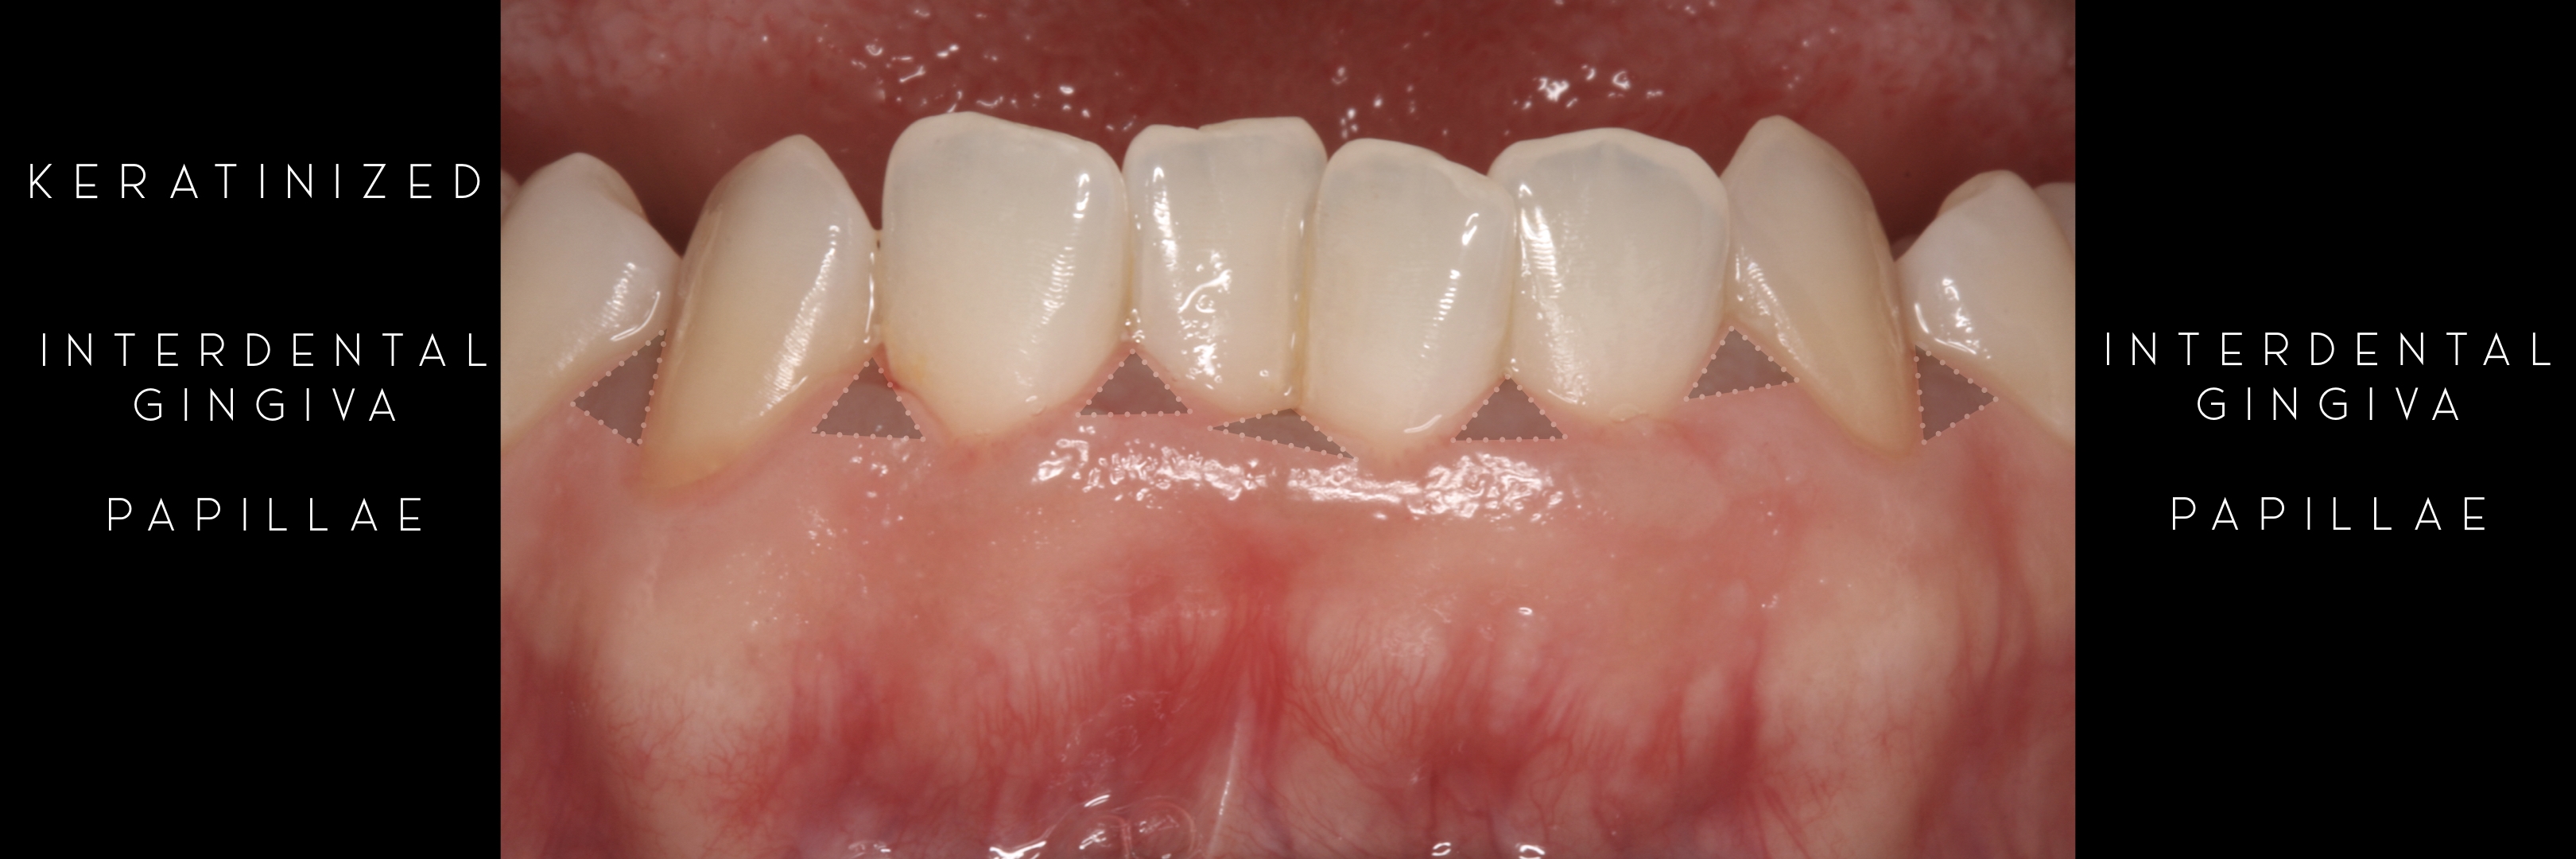

Attached Gingiva, Marginal Gingiva,

Interdental Gingiva

Keratinized Gingiva

KERATINIZED gingiva includes

the free gingiva

(marginal gingiva & papillae)

and the attached gingiva extending from the gingival mar­gin to the mucogingival junction.